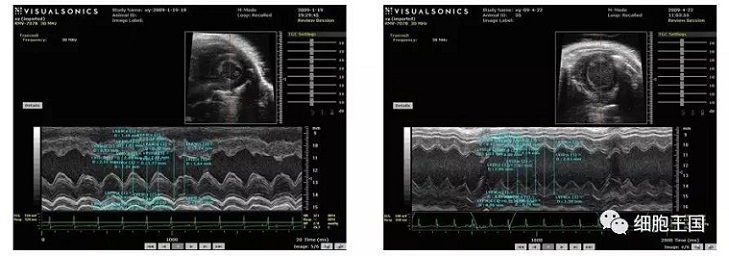

超聲心動圖顯示對照組左室舒張期容積低于移植組